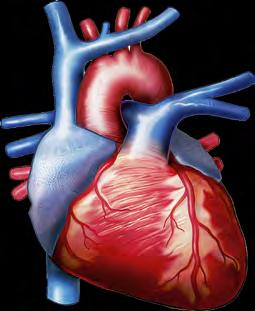

організмі людини виокремлюють такі фізіологічні системи органів: опорно-рухова, яка забезпечує формування структури тіла, механічний захист органів, здатність

до різноманітних рухів; дихальна, яка постачає до організму кисень та

кровоносна, яка вможливлює транспортування різноманітних речовин по організму, а також бере участь

(іл. 56 ). Опорно-рухова система містить кістки й скелетні м’язи. Вона виконує захисну, опорну, рухову, метаболічну, кровотворну й терморегуляційну функції (іл. 58).